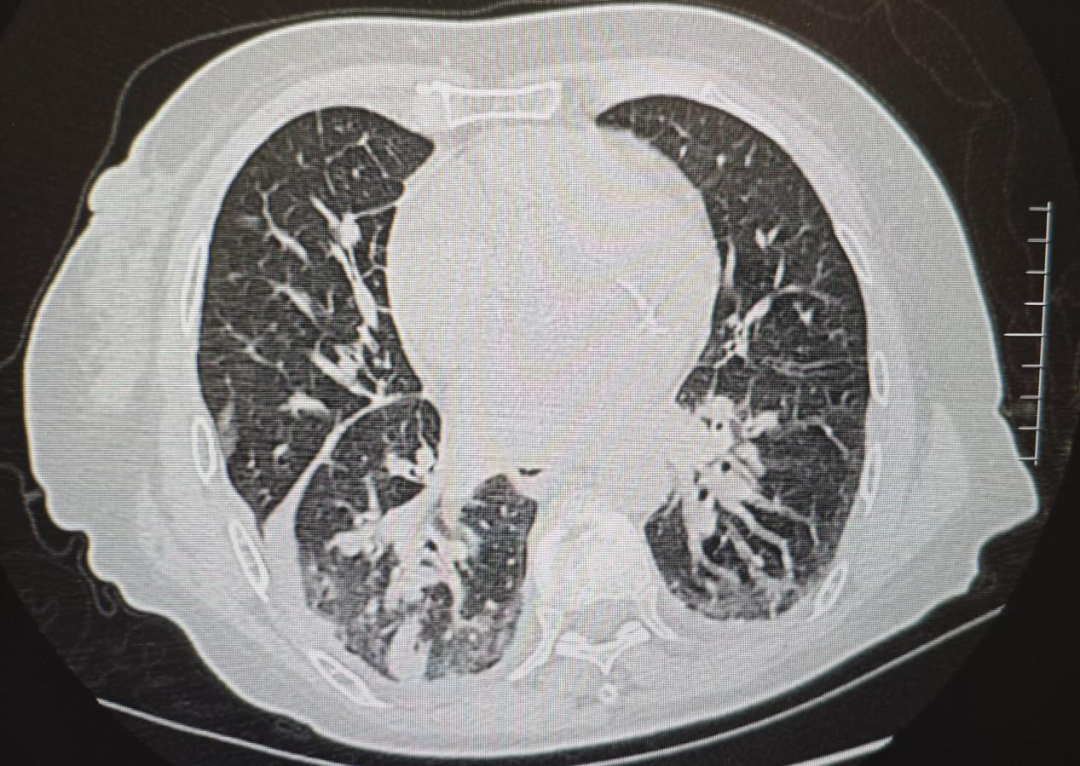

速看!流感暗箭——解码隐匿的致命连击

感染性疾病科 上饶市人民医院